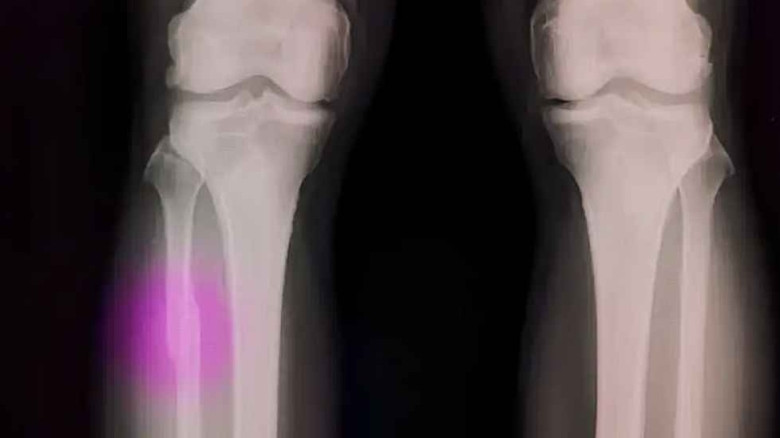

গ্লু গানেই জোড়া লাগবে ভাঙা হাড়, বলছেন গবেষকরা

অস্ট্রেলিয়ার একদল গবেষক ভাঙা হাড় জোড়া লাগানোর নতুন প্রযুক্তি উদ্ভাবন করেছেন, যা চিকিৎসাবিজ্ঞানে বড় ধরনের পরিবর্তন আনতে পারে। তারা বিশেষ ধরনের জৈব আঠা তৈরি করেছেন এবং সেটি প্রয়োগের জন্য থ্রি-ডি প্রিন্টিং কলমের মতো একটি যন্ত্র তৈরি করেছেন, যার নাম দেওয়া হয়েছে ‘বায়োপেন’।

এই প্রযুক্তির মাধ্যমে ভাঙা হাড়ের স্থানে বিশেষ জেল বা আঠা প্রয়োগ করা হয়। এরপর অতিবেগুনি রশ্মি বা নির্দিষ্ট আলো প্রয়োগ করলে আঠাটি দ্রুত শক্ত হয়ে হাড়ের মতো দৃঢ় কাঠামো তৈরি করে।

গবেষকদের মতে, এই পদ্ধতিতে হাড় দ্রুত জোড়া লাগতে পারে এবং রোগীদের দীর্ঘদিন প্লাস্টার বা ধাতব যন্ত্রের ওপর নির্ভর করতে নাও হতে পারে। অস্ত্রোপচারের সময় চিকিৎসকেরা সরাসরি ক্ষতস্থানে এই আঠা ব্যবহার করে আরও নিখুঁতভাবে হাড় স্থির করতে পারবেন বলেও তারা আশা করছেন।

বর্তমানে হাড় ভাঙার চিকিৎসায় প্লাস্টার, ধাতব পাত, স্ক্রু বা অস্ত্রোপচার প্রচলিত পদ্ধতি হলেও নতুন এই উদ্ভাবন চিকিৎসা ব্যবস্থায় যুগান্তকারী পরিবর্তন আনতে পারে বলে মনে করছেন বিশেষজ্ঞরা।

চিকিৎসা প্রযুক্তির দ্রুত অগ্রগতির ধারাবাহিকতায় ‘বায়োপেন’ ভবিষ্যতে অর্থোপেডিক চিকিৎসায় গুরুত্বপূর্ণ ভূমিকা রাখবে বলে আশা করছেন বিজ্ঞানীরা। তাদের মতে, একসময় হয়তো প্লাস্টার ব্যবহারের প্রচলন ইতিহাসের অংশ হয়ে যাবে।